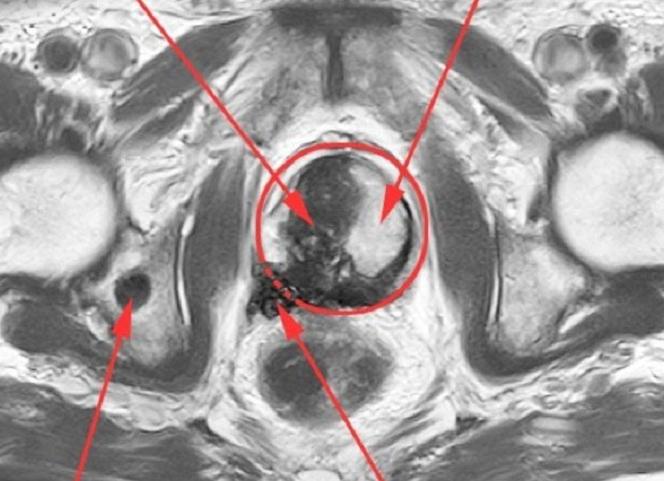

Воспалительные процессы и новообразования в тканях простаты становятся различимыми при использовании магнитно-резонансной томографии.

МРТ позволяет четко выявить глубинную дискретность простаты, топографию, размер, очертания и другие параметры патологического образования.

- Если очаги с низкой интенсивностью изображения имеют конусовидную форму и более четкие контуры, подозрение падает на простатит.

- При определении одного из признаков (выбухание ткани простаты, нарушение симметрии сосудисто-нервных пучков, несинхронных сигналах от семенных пузырьков) лечащему врачу направляются результаты о злокачественной опухоли в простате. Достоверность определения метастазов раковой опухоли при использовании МРТ составляет 99%.